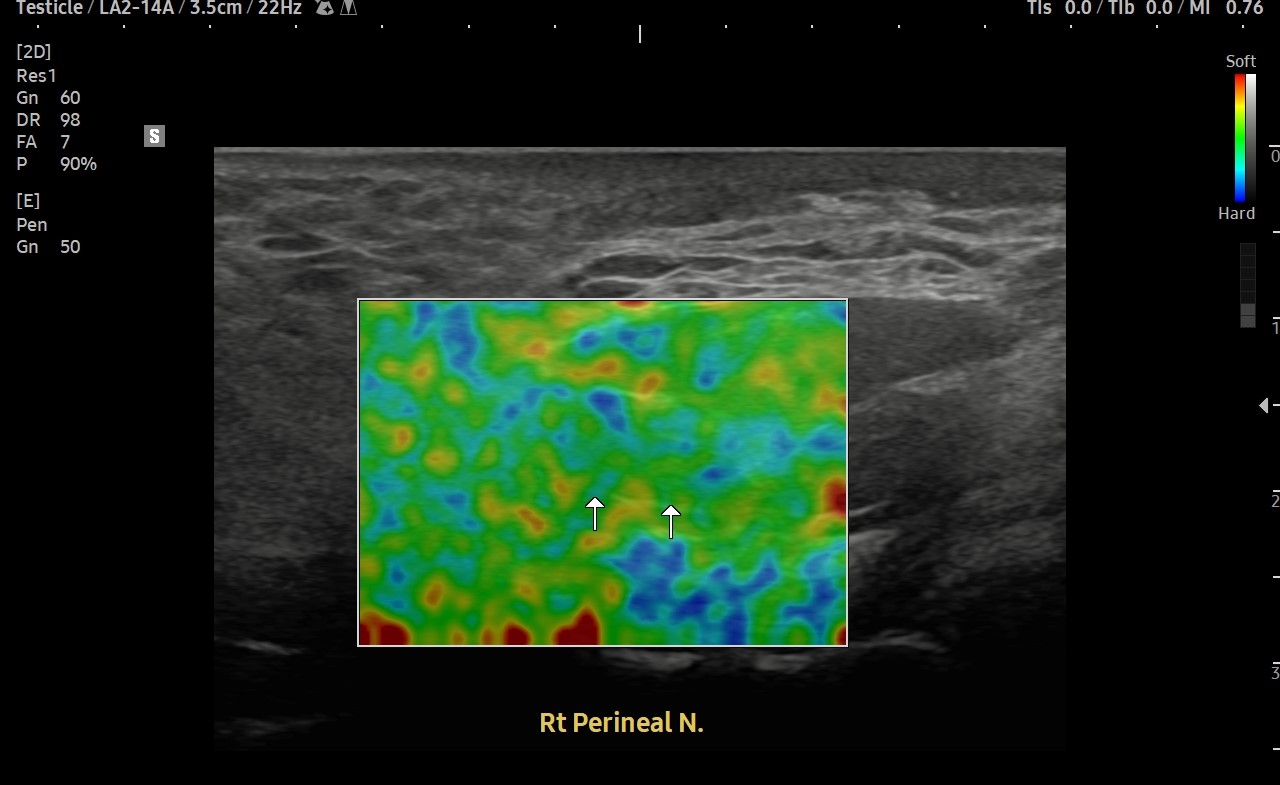

[치료 전]

[치료 후]

- 치료횟수 : 20 회